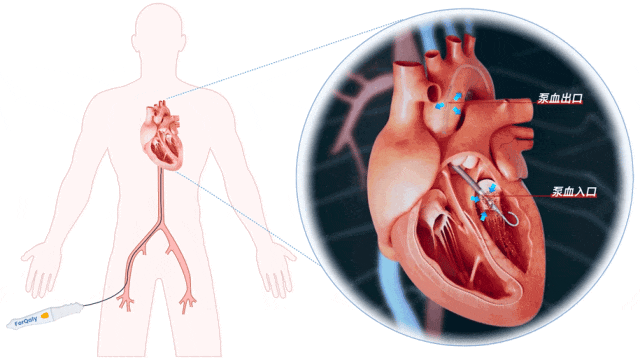

ECMO术后患者仍存在顽固性气促、粉红色泡沫痰,心脏彩超提示左心胀满、血流瘀滞。经团队讨论,单纯ECMO支持会持续加重左心后负荷,决定紧急置入SynFlow®3.0经皮跨瓣膜心室辅助系统。

操作要点:DSA引导下穿刺左侧股动脉,置入配套可撕开导管鞘;导管跨主动脉弓及主动脉瓣,DSA实时定位后启动系统。

SynFlow®3.0产品介绍

SynFlow®3.0经皮跨瓣膜心室辅助系统,由丰凯利医疗器械(上海)有限公司自主研发,是中国首个进入NMPA创新医疗器械特别审批程序的介入式心室辅助产品。

该产品开创性地实现了四大技术突破:

1. 卓越的血流动力学性能

创新的叶轮结构设计,兼容14F可撕开鞘,其峰值流量>4.0L/min。保证高流量的同时极大得减小对血细胞的机械损伤(FHb<10mg/dL)。